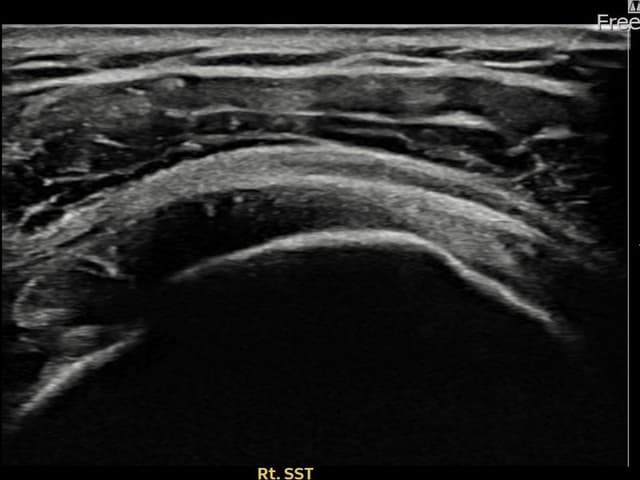

治療実績 — 超音波エビデンス

実際の患者様の施術前後の超音波画像。

手術なしで実現できる回復をご確認ください。

すべての超音波画像は患者様の同意を得て掲載しています。個人差があり、同一の結果を保証するものではありません。

[経過期間: 24.04.26~24.07.05]

[縫縮術] 超音波検査にて右 棘上筋腱 관절면측 광범위 部分断裂(16mm × 5mm (腱厚の約75%欠損))を確認。縫縮術施行後、腱の連続性が回復し、日常生活に復帰されました。